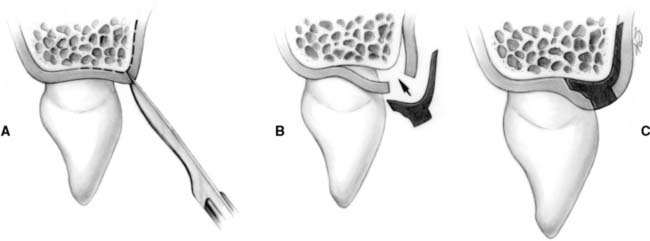

Surgical crown lengthening or extension (Fig. 6-16) may be indicated to improve the appearance of an anterior tooth or when the clinical crown is too short to provide adequate retention without the restoration’s impinging on the normal soft tissue attachment61 or biologic width.* This attachment averages approximately 2 mm in width, and any restoration that impinges on it may cause bone loss because of the effort of the host to maintain the 2 mm distance. If impingement occurs in an interproximal area, it can lead to problems with plaque control and possible osseous resorption.62-64 Therefore, from the standpoint of prognosis, the biologic width should never be compromised.

Fig. 6-16 Surgical crown lengthening. A, Fractured and carious second premolar. B, Reflection of a flap and removal of granulation tissue. C, Bone removed on the mesial aspect to increase the distance to the fracture site to 3.5 mm. D, Distally the bone is removed so that there will be 3.5 mm from the caries to the alveolar crest. E, Healing after the surgical crown lengthening. F, Final crown restoration after cementation, before restoration of the sextant with a removable dental prosthesis.

In some patients, an apparently unsalvageable tooth with extensive subgingival caries, a subgingival fracture, or root perforation resulting from endodontics can be successfully restored after crown lengthening. Crown lengthening increases the crown/root ratio, however, and a pretreatment decision must be made about whether the tooth should be removed or restored.

Crown lengthening may be accomplished either surgically or with combined orthodontic-periodontic65-69 techniques, depending on the patient and the dental situation.

It is sometimes possible to achieve an effective increase in crown length by gingivectomy or removal of gingiva by electrosurgery alone (see Fig. 6-16), although osseous recontouring is most often needed to prevent encroachment of the prosthesis on the biologic width. For these procedures, a full-thickness mucoperiosteal flap is reflected, and the osseous resection creates 3.5 to 4.0 mm of space between the gingival crest and the margin of the existing restoration or carious lesion.61,70 In these instances, however, the following factors should be considered:

Restoration of a tooth that has undergone crown lengthening is commonly undergone in 4 to 6 weeks after the surgical procedure. A clinicale study73 has demonstrated that the biologic width and the position of the free margin of the gingivae exhibited no change at 3 to 6 months after surgery. Therefore, it may be advisable to provisionally restore that tooth in question, either before or immediately after surgical crown lengthening, and subsequently fabricate the final restoration after 3 months.

Although surgical crown lengthening may not be a panacea for fractured, perforated, or badly decayed teeth, it can help solve difficult and/or complex restorative problems when used with proper clinical judgment.